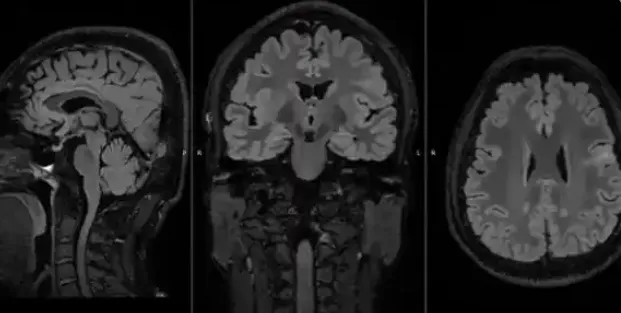

近日,兰州大学第二医院神经外科正式启动甘肃省首个植入式闭环脑部采集刺激系统(ANS)脑机接口GCP项目,并成功完成省内首例脑机接口临床手术。这一突破性进展不仅填补了甘肃省在脑机接口临床应用领域的技术空白,更标志着我国药物难治性癫痫治疗正式迈入“精准闭环调控”的全新阶段。

从细分市场看,2023年超声影像诊断设备、X射线计算机体层摄影设备(CT)和磁共振成像设备(MRI)是公开中标金额占比最大的三个领域,合计超过75%的市场份额,其中超声影像诊断设备和CT的国产化率进一步提升。迈瑞、联影、东软、开立、万东等国产品牌代表,已跻身各细分市场前列,国产设备替代进口产品的趋势渐显。